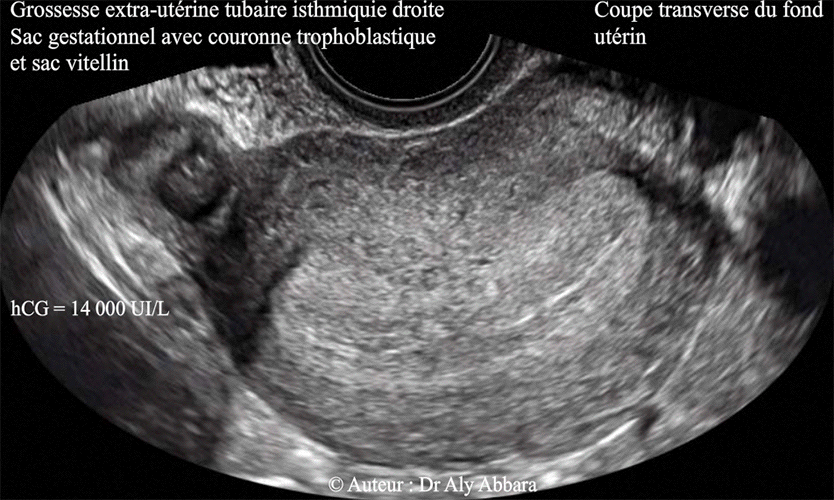

• Image échographique montrant une grossesse extra-utérine implantée au niveau la partie proximale de la portion, isthmique de la trompe droite.

Sur l'image échographique on constate que cette grossesse de 20 mm de grand axe est en contact avec le bord externe de la corne droite de l'utérus. Le sac gestationnel est identifiable par sa couronne trophoblastique et sa vésicule vitelline.

Le dosage de β-hCG plasmatique dans l'heure qui a précédé l'examen échographique montrait un taux égale à 14 000 UI/l.